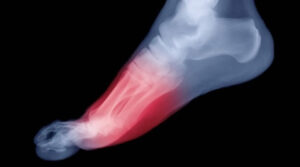

La metatarsalgia es el dolor o inflamación en la planta de los pies, cerca del inicio los dedos que se acentúa al caminar, al correr o al utilizar algunos tipos de zapatos (especialmente con el tacón).

El metatarso es la zona del pie sobre la que más peso apoyamos cuando corremos o caminamos. Es un punto propenso a sufrir diferentes lesiones y dolores que pueden influir en nuestra forma de pisar, especialmente cuando practicamos ejercicio.

En la parte anterior del pie hay cinco huesos largos llamados metatarsianos donde se unen las falanges para formar los dedos. Uno de estos huesos es más grueso que el resto, el que corresponde al dedo gordo que es donde aparecen los juanetes. Los metatarsianos son los responsables de soportar el peso del cuerpo para realizar el despegue del pie del suelo, recibiendo mucha presión durante la ejecución del paso.

Este aumento de presión constante y repetitiva en la zona metatarsal produce dolor e inflamación y una sensación punzante que empeora al caminar, ya sea descalzo, sobre una superficie dura o con calzado de poca suela. Es habitual que en las zonas de máxima presión aparezcan durezas o callos.